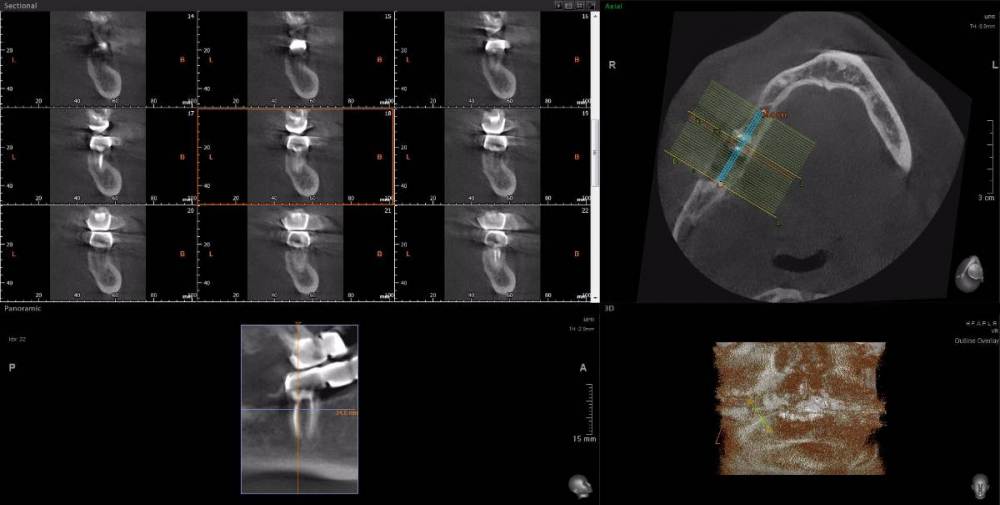

Dude Опубликовано 1 апреля, 2021 Автор Поделиться Опубликовано 1 апреля, 2021 https://disk.yandex.ru/d/6d0pmZ1zArn1Og Так? Ссылка на комментарий